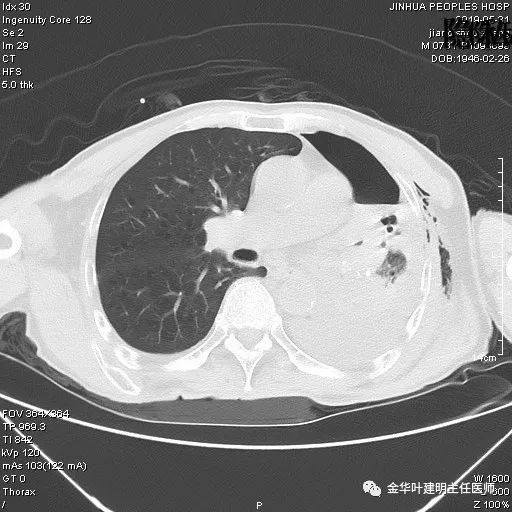

患者,男性,73岁,金华人。因“咳嗽咳痰伴胸闷2月,检查确诊左肺癌1周”入院。气管镜: 气管支气管内较多脓性分泌物,左肺上叶前段管腔新生物,局部活检、毛刷。气管镜病理:(左肺活检)鳞癌。阅胸部CT见左上叶开口处新生物,考虑需左上叶袖式切除及淋巴结清扫。具体CT表现如下:

考虑左侧大量胸腔积液,遂进一步胸部CT检查:

以上是肺窗表现,下面为纵隔窗影像: